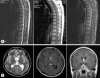

We report a case of intracranial dissemination developing approximately 4 months after partial removal of a spinal cord anplastic astrocytoma in a 22-year-old male. He presented with paraplegia on initial admission at a local hospital. Spinal magnetic resonance (MR) images disclosed multiple intramedullary lesions at the T3-11. The tumor was partially removed. The final histologic diagnosis was anaplastic astrocytoma. Four months after the operation, he was admitted with the symptoms of headache and deterioration of consciousness. MR images showed enhanced lesions in the anterior horn of the left lateral ventricle, and septum pellucidum. He underwent computed tomography-guided stereotactic biopsy and histological appearance was consistent with anaplastic astrocytoma. The clinical course indicates that the tumor originated in the spinal cord and extended into the subarachnoid space, first the spinal canal and later intracranial.